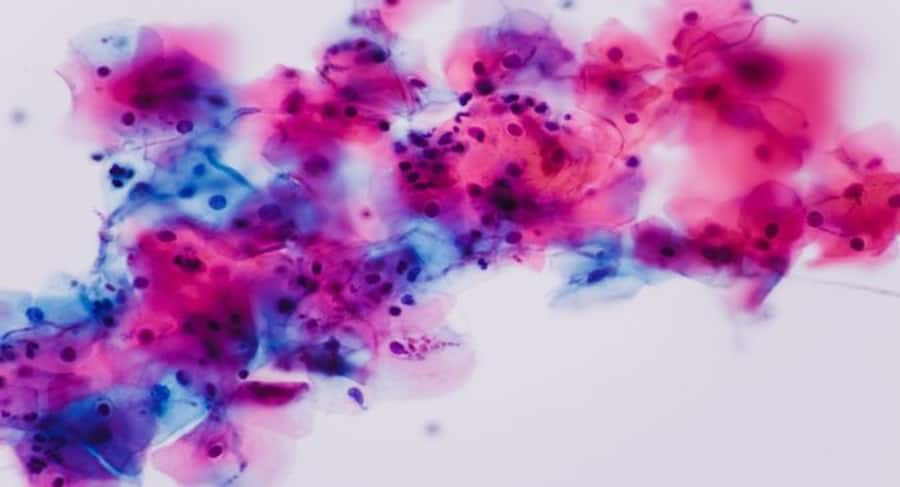

It is a fungal infection caused due to an abnormal overgrowth of the fungus Candida albicans.©Shutterstock

If you experience from sudden headaches, yeast infection, fatigue, itching, etc then you must be suffering from Candida or Candidiasis. It is a fungal infection caused due to an abnormal overgrowth of the fungus Candida albicans. Already many people have this pathogen inside their bodies but by certain good microbes within the body, it is kept under control. At times the balance of these good microbes in the digestive tract gets disturbed because of various reasons. When this happens the Candida albicans spread at a rapid pace, especially a huge portion of the digestive tract, which leads to the above-mentioned symptoms.